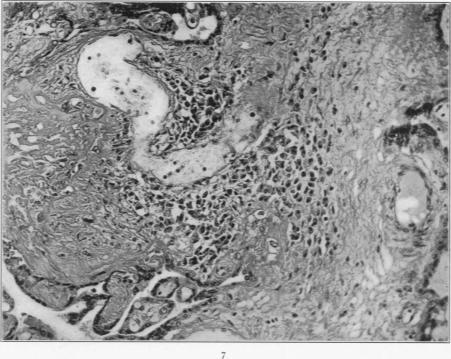

Inclusion disease in childhood.

Arch Dis Child. 1951 Dec;26(130):588-600. doi: 10.1136/adc.26.130.588.

[Pathology of the cytomegaly; inclusion body disease, virus disease of the salivary glands].

Virchows Arch Pathol Anat Physiol Klin Med. 1954;325(5):596-623. doi: 10.1007/BF00955188.